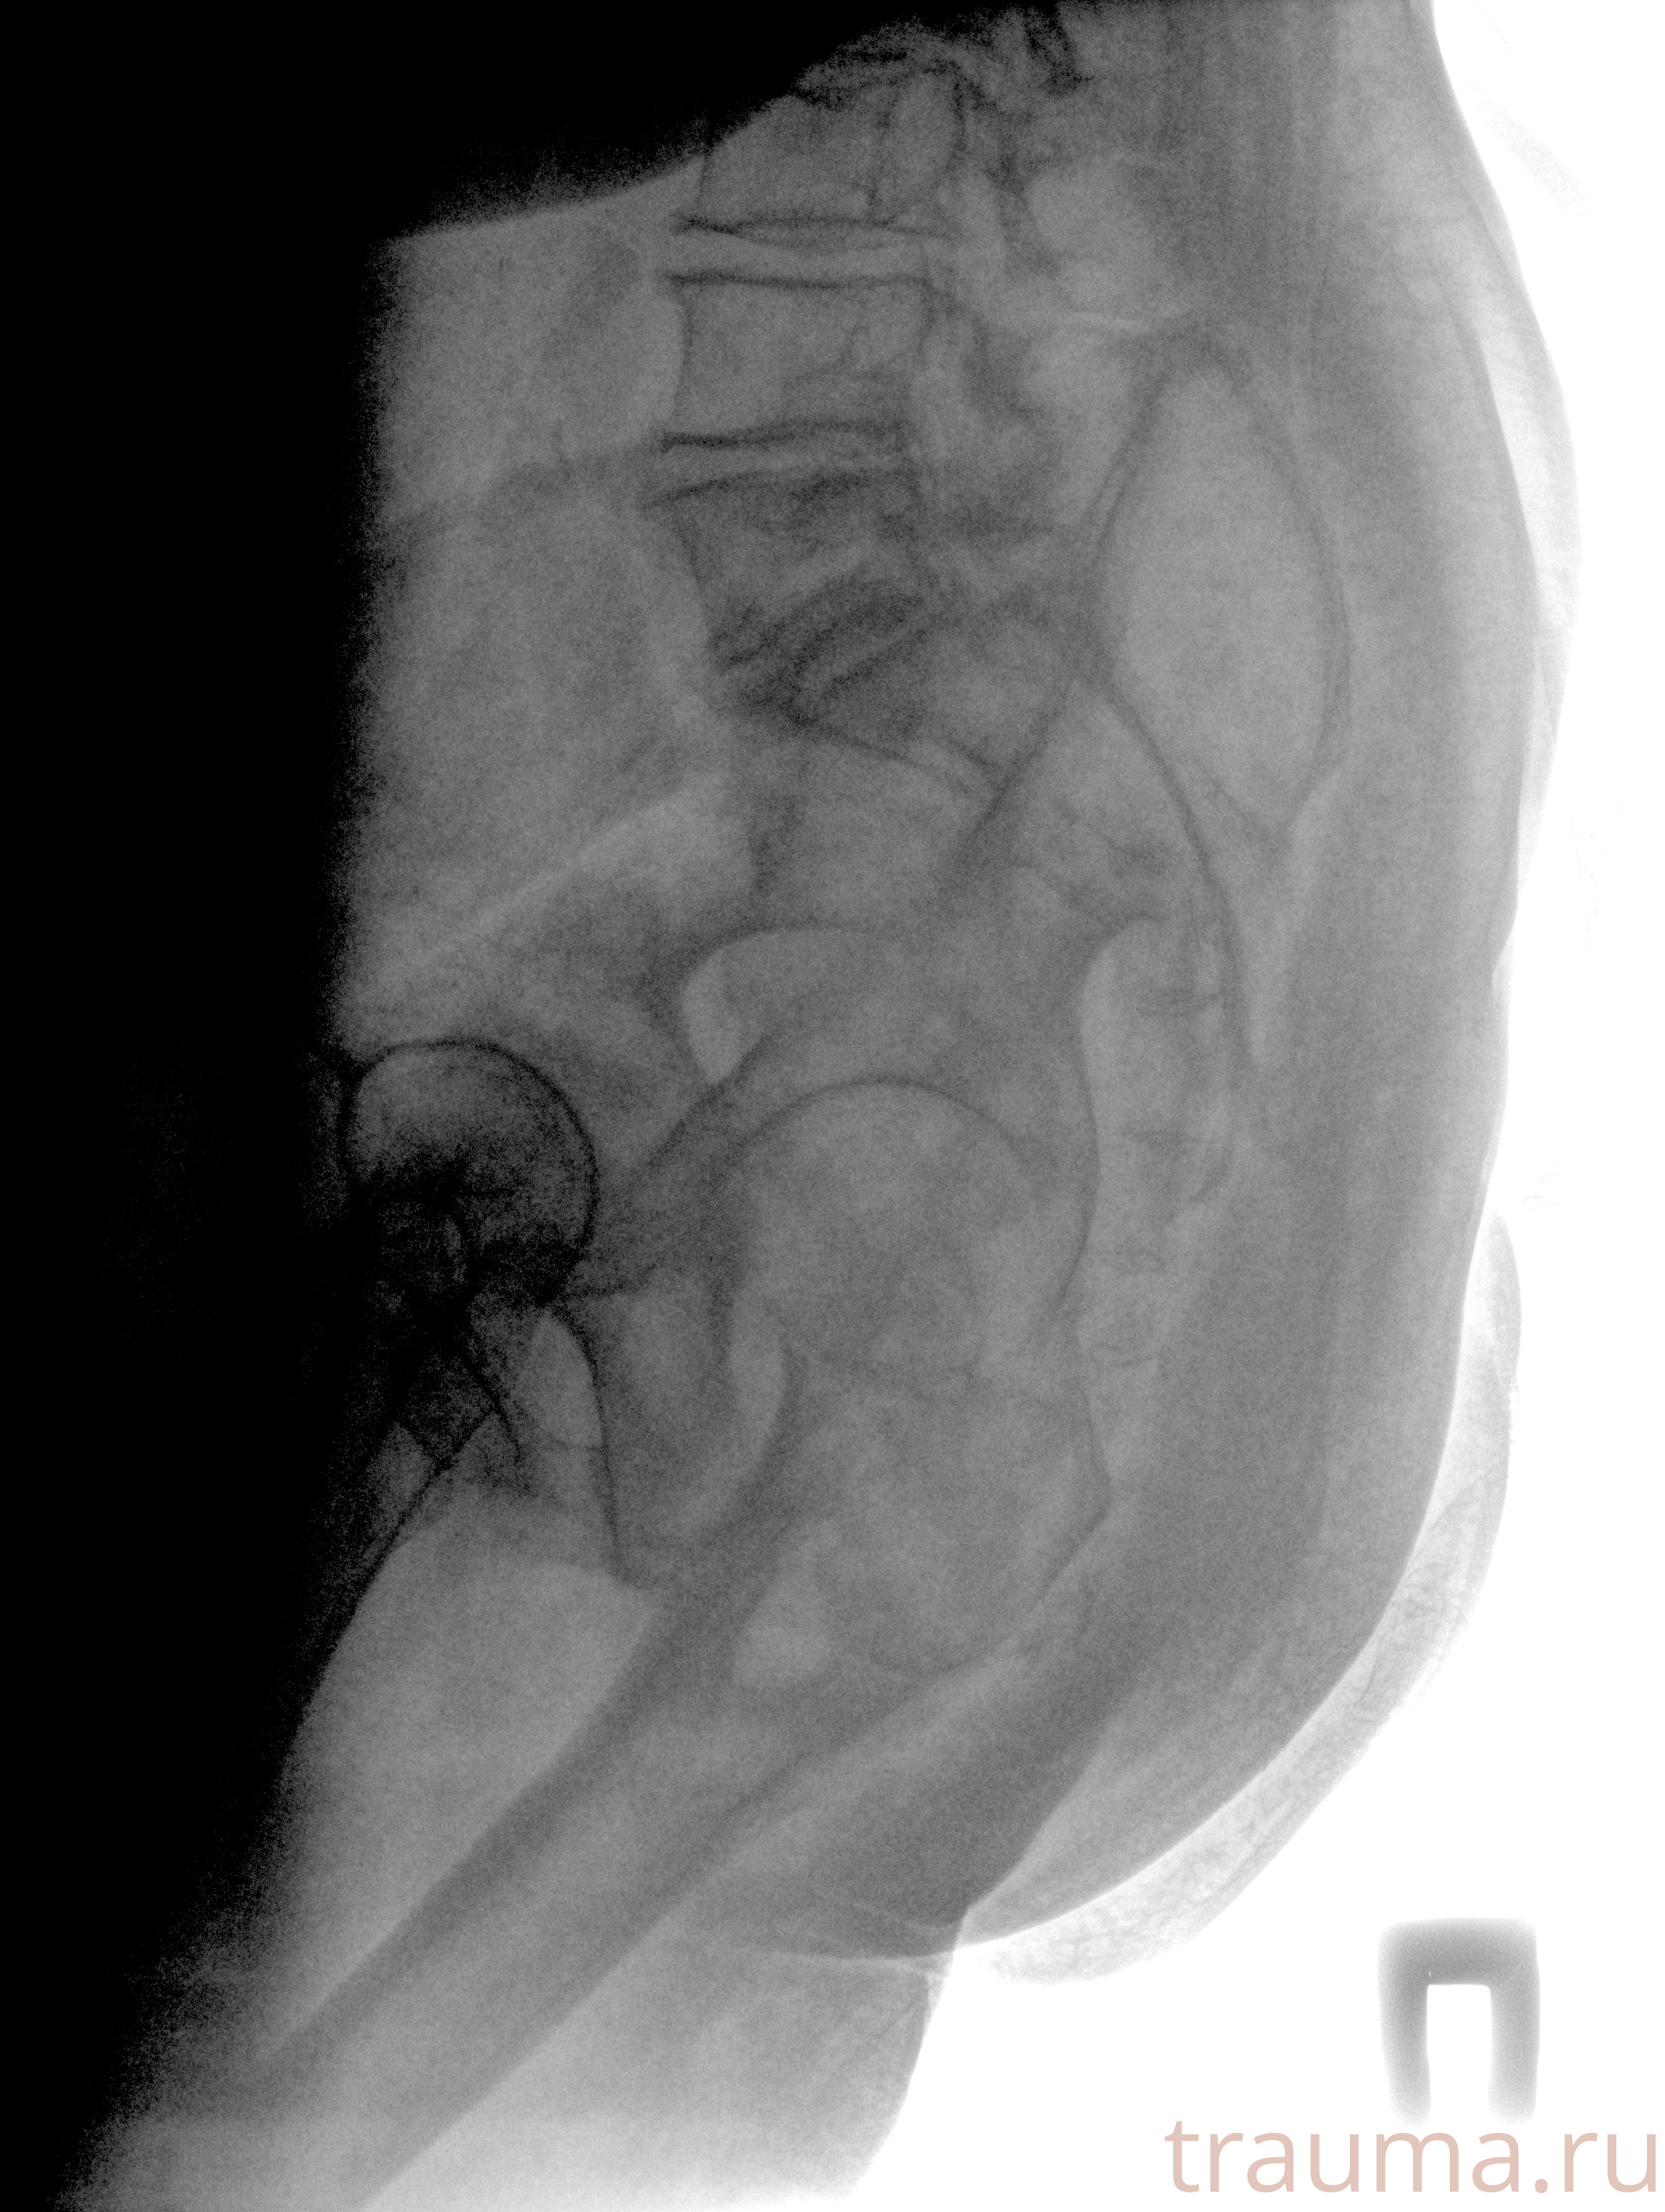

Рентген на дому: по вашему адресу приезжает врач-рентгенолог, травматолог-ортопед с мобильным рентгеновским аппаратом, проводит диагностику травмы или заболевания, делает необходимые рентгенограммы, дает рекомендации по дальнейшему лечению. Получить качественные снимки в домашних условиях возможно благодаря уникальной методике, разработанной МосРентген Центром для института  Склифосовского

при переломе шейки бедра и пневмонии от компании МосРентген Центр - партнера Института имени Склифосовского